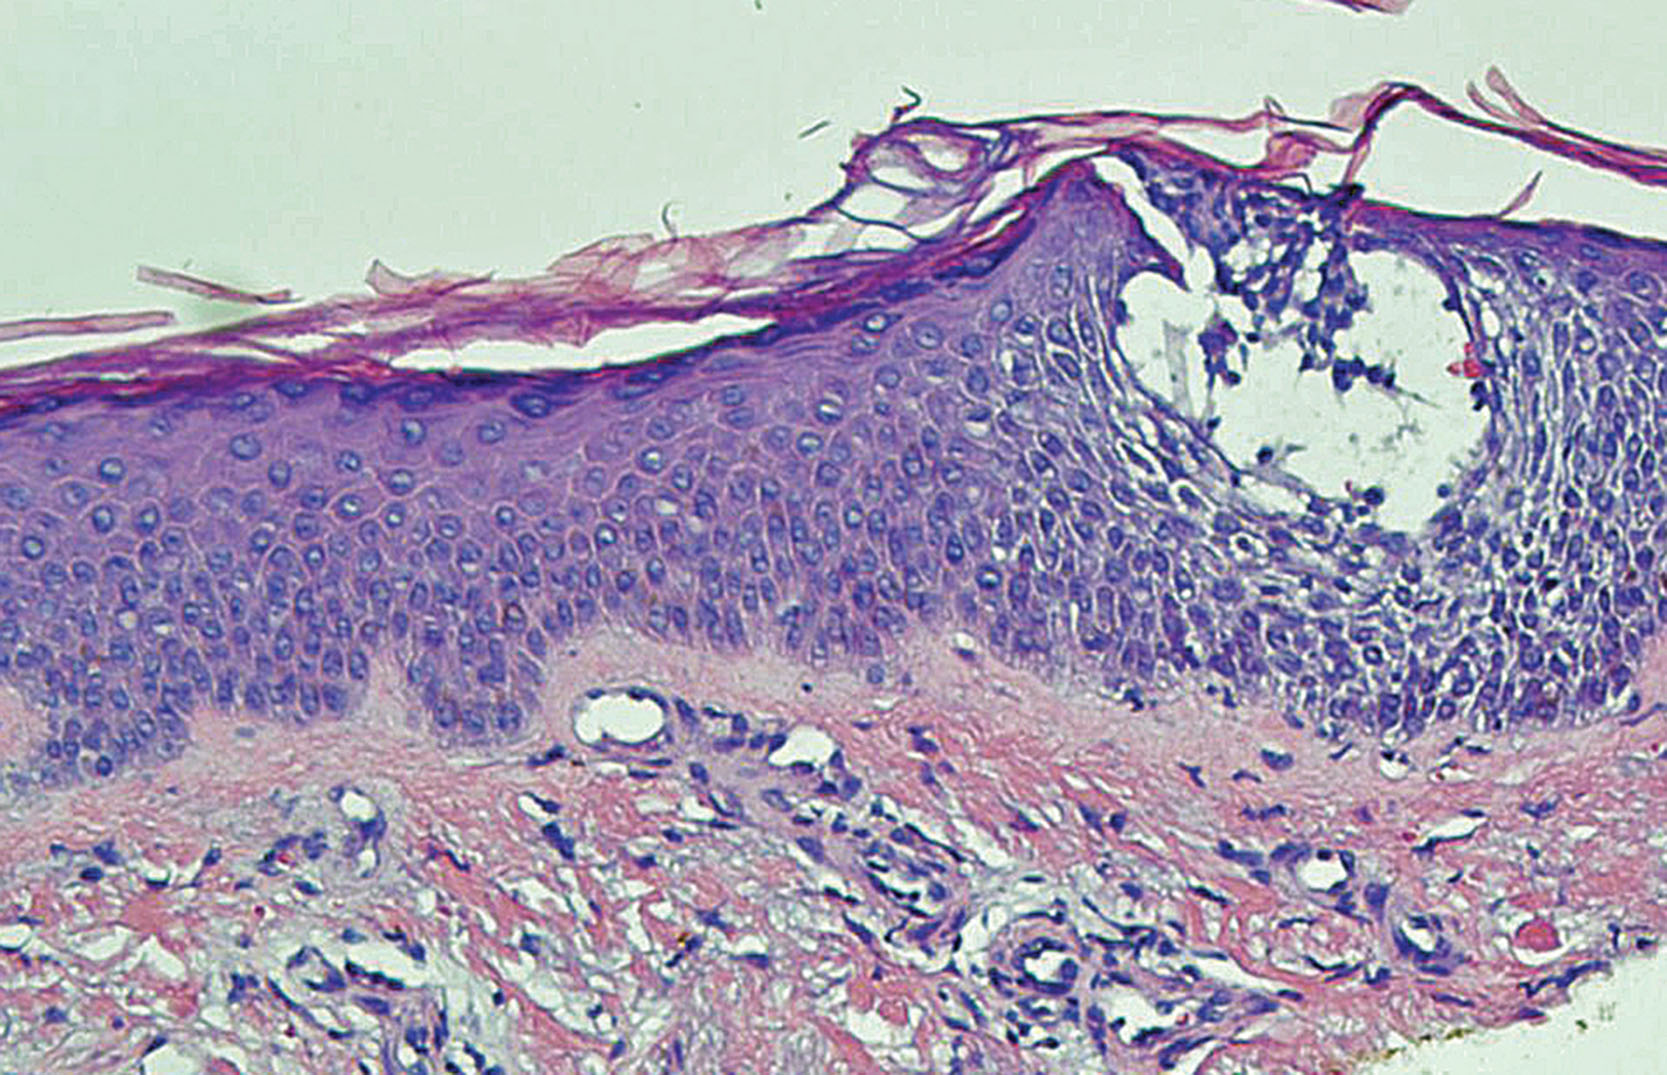

In the nonvesicular lesional skin of atopic dermatitis, one can commonly visualize a picture of inflammation with the following findings under the microscope ( Fig. 3.1 ). In the acute inflammatory lesion, the epidermis shows psoriasiform hyperplasia and intercellular edema. Epidermal and dermal white blood cell infiltrations are composed primarily of lymphocytes with occasional monocytes/macrophages, neutrophils, eosinophils, and basophils. Mast cells and Langerhans cells are present. We can also observe some vascular changes, including endothelial cell hypertrophy, rare endothelial mitosis, and large activated nuclei, suggesting a process of angiogenesis. In chronically inflamed lesion, the epidermis is visibly different from the acute lesion, with the presence of hyperkeratosis and dyskeratosis besides psoriasiform hyperplasia. Varying degrees of intercellular edema and a few lymphocytes are present. In the dermis there are a moderate number of lymphocytes and monocytes/macrophages. The number of mast cells significantly increases ( ). The thickness of the granular layer of the epidermis in atopic dermatitis lesion can be similar to that of normal individuals, unless atopic dermatitis occurs in a person who has filaggrin gene mutation with a corresponding reduction of granular cell layer ( ). More details of filaggrin mutation in atopic dermatitis are discussed in Chapter 5, Chapter 11 .